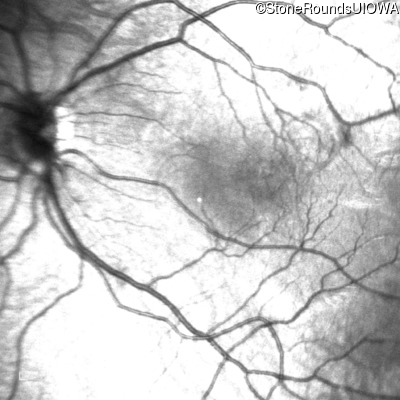

Infrared Fundus Photograph - Left - 20/80

Exemplar